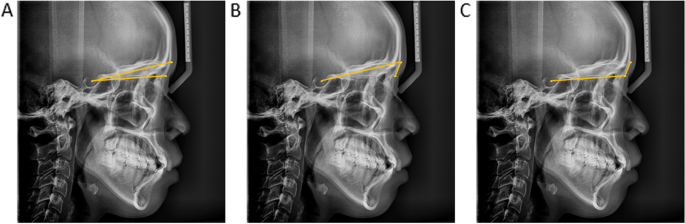

Figure 1 from Angular Relationship between Frankfort Horizontal ...